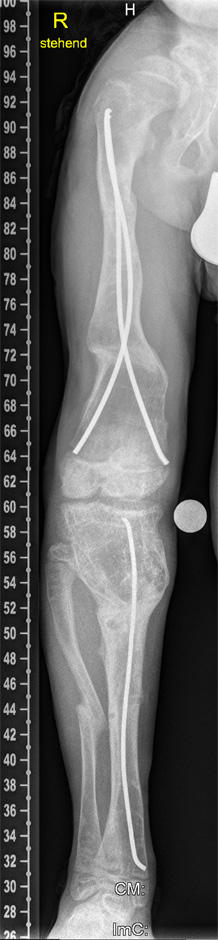

Figure 5

After distal femoral and proximal tibial osteotomy, the severe varus deformity was corrected by gradual distraction using the Taylor Spatial Frame™.

Figure 6

After consolidation and removal of the frame, a prophylactic nailing of the right femur and tibia was performed to obtain the correction.